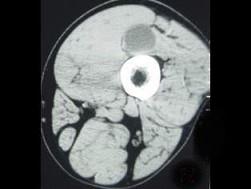

问题 男,48岁,左大腿上段后部轻度胀痛,轻压痛,无明确外伤史,请结合所提供的图像,选择最佳选项 ( )

选项 A、腱鞘囊肿 B、腱鞘脓肿 C、皮脂腺瘤 D、脂肪瘤 E、表皮样囊肿

答案 A